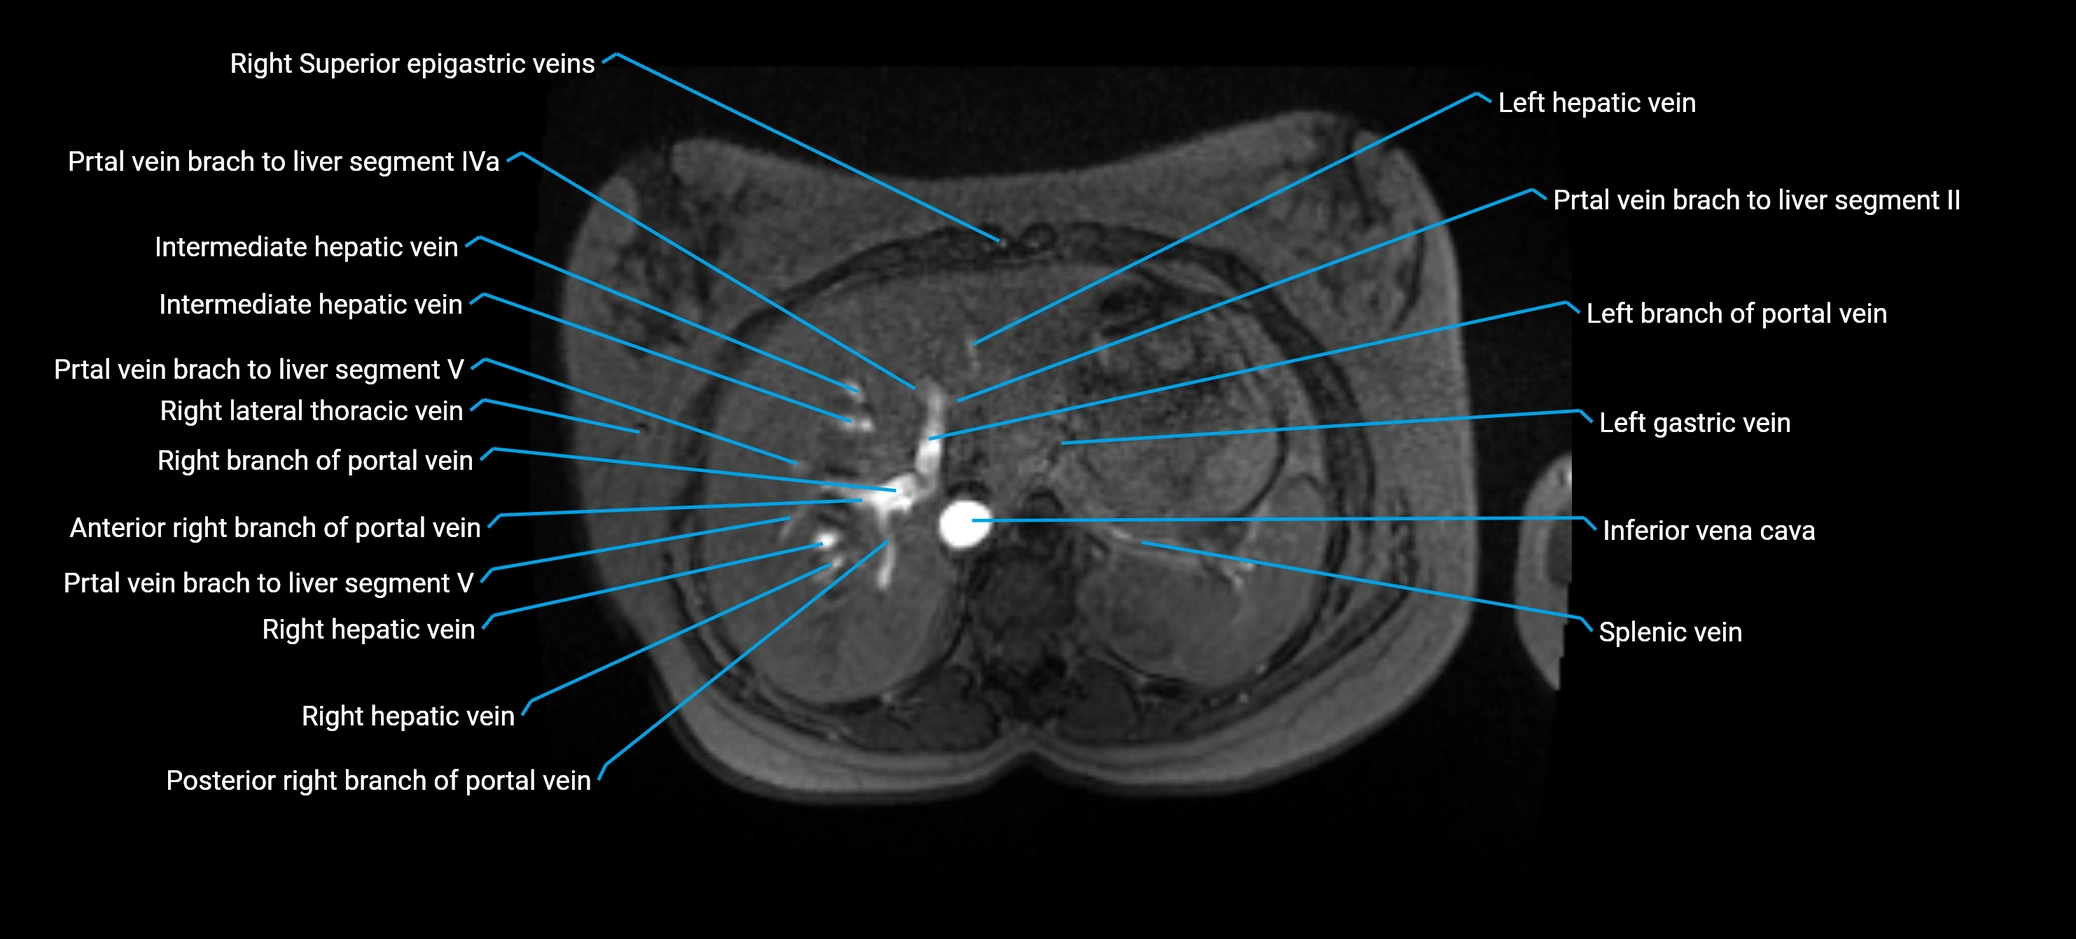

The anterior right branch of the portal vein is a major intrahepatic division of the right portal vein. After the main portal vein bifurcates into right and left branches, the right portal vein divides into anterior and posterior segmental branches.

The anterior right branch supplies the anterolateral liver segments (Segment V) and anteromedial liver segments (Segment VIII) within the right hepatic lobe. It operates as a key vascular route delivering nutrient-rich portal venous blood to the central and superior right liver.

This segmental vasculature is of major importance in hepatic surgery, embolization, segmental resection, transplantation, and imaging-based liver segmentation.

MRV TOF (Time-of-Flight MR Venography):

• Appears as a bright, high-signal vascular channel representing flowing blood

• Clearly shows branching pattern of right portal vein into anterior and posterior branches

• Best in coronal or axial reconstructions for segmental mapping

• No need for contrast, relies on flow-related enhancement

Post-Contrast T1 Fat-Sat GRE:

• Enhances brightly and homogeneously during the portal venous phase

• Clearly delineates branching into segments V and VIII

• Best sequence for evaluating patency, caliber, and anatomic variants

• Early arterial phase: minimal enhancement

• Delayed phase: gradual washout but still brighter than hepatic parenchyma